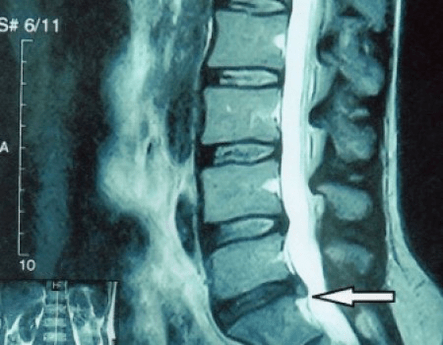

Da die Bandscheiben selbst nur mittels CT oder MRT sichtbar sind, sind Magnetresonanztomographie und Röntgen-Computertomographie angezeigt, um den inneren Aufbau von Knorpel und Formationen wie Vorwölbungen und Hernien abzuklären. Somit wird mit Hilfe dieser Methoden eine genaue Diagnose gestellt und das Tomographieergebnis ist ein Hinweis und sogar ein aktueller Leitfaden für die chirurgische Behandlung eines Leistenbruchs in der neurochirurgischen Abteilung.

- Wenn Sie einen Leistenbruch haben, müssen Sie ihn dynamisch überwachen, regelmäßige MRTs durchführen, eine Vergrößerung vermeiden oder eine moderne minimalinvasive chirurgische Behandlung durchführen, da alle konservativen Methoden zur Behandlung einer Verschlimmerung der Osteochondrose ausnahmslos den Leistenbruch an Ort und Stelle belassen und nur vorübergehende Symptome beseitigen: Entzündungen, Schmerzen, Brennen und Muskelkrämpfe.